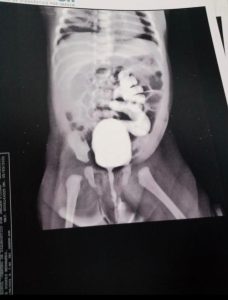

A pequena Amélie foi diagnosticada ainda na gestação, com um refluxo vesicoureteral de grau V. Desde o nascimento, a criança tem sido acompanhada por médicos, realizado exames e feito fisioterapia para estimular a bexiga a esvaziar e não ocorrer o refluxo.

Segundo Raylda Karla, o refluxo faz com que a pequena Amélie perca lentamente a função renal, e o rim, uretra e bexiga sofrem uma dilatação.

“Basicamente, ela vai perdendo a função renal à medida que os meses passam. Isso aconteceu porque a urina, que é produzida nos rins, chega a bexiga por meio do ureter. Esse problema causa uma dilatação no rim, ureter e bexiga, e essa dilatação acaba promovendo um refluxo da urina que deveria ser expelida”, disse Raylda Karla, mãe de Amélie.